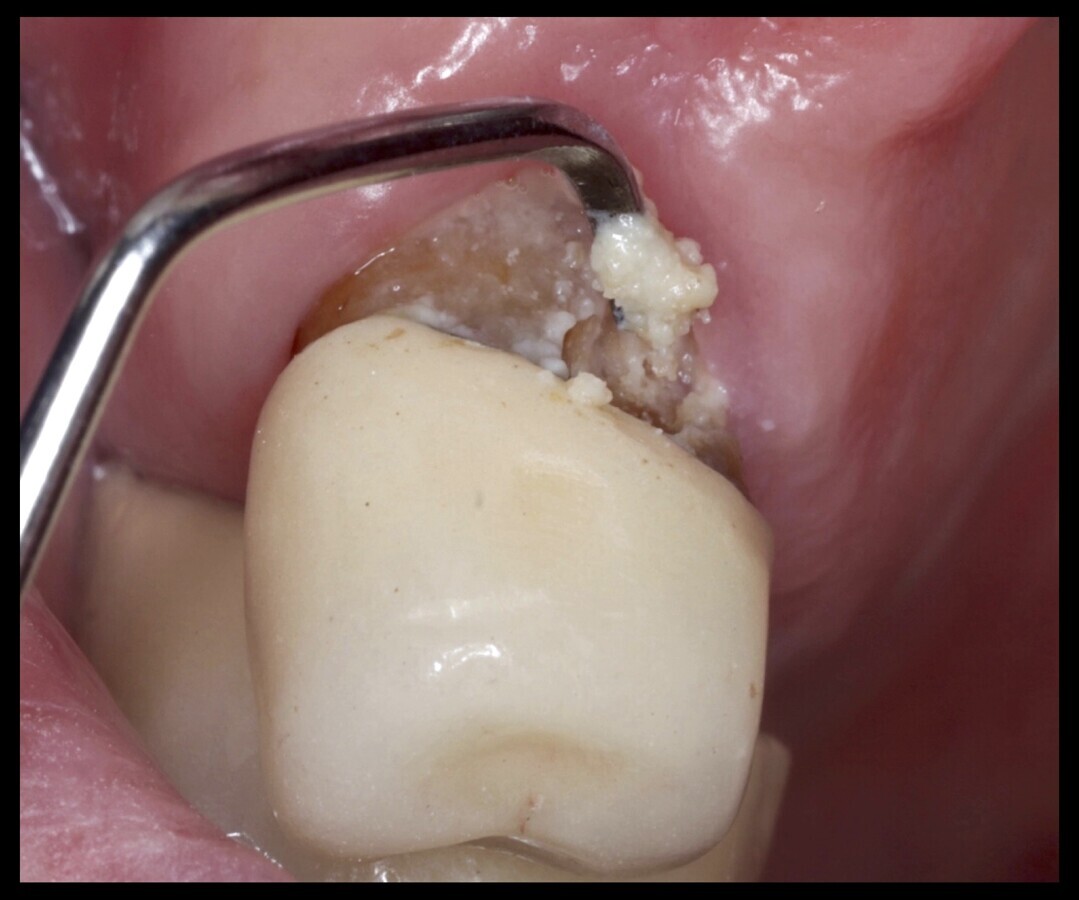

Caries radicular y xerostomía en un paciente que toma carbidopa-levodopa para el tratamiento del Parkinson.

La mayoría de los medicamentos asociados con la disfunción de las glándulas salivares pertenecen a la categoría principal del sistema nervioso en el ATC. Según la literatura médica, algunos de los medicamentos más citados con efecto en el sistema nervioso incluyen: tolterodina, duloxetina, quetiapina, bupropión, olanzapina, clozapina, fluoxetina, paroxetina y sertralina, venlafaxina. Además, se han observado efectos similares en la función de las glándulas salivares con fármacos urológicos como la oxibutinina, tolterodina y solifenacina.